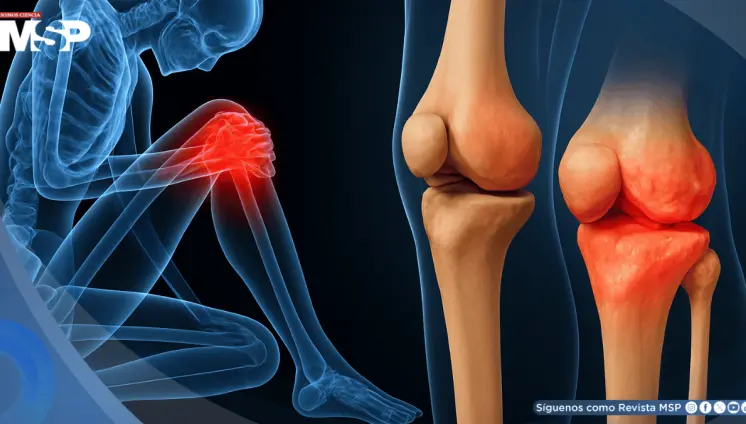

En esta condición, la cápsula del hombro se vuelve más gruesa y rígida, formando bandas duras de tejido conocidas como adherencias.